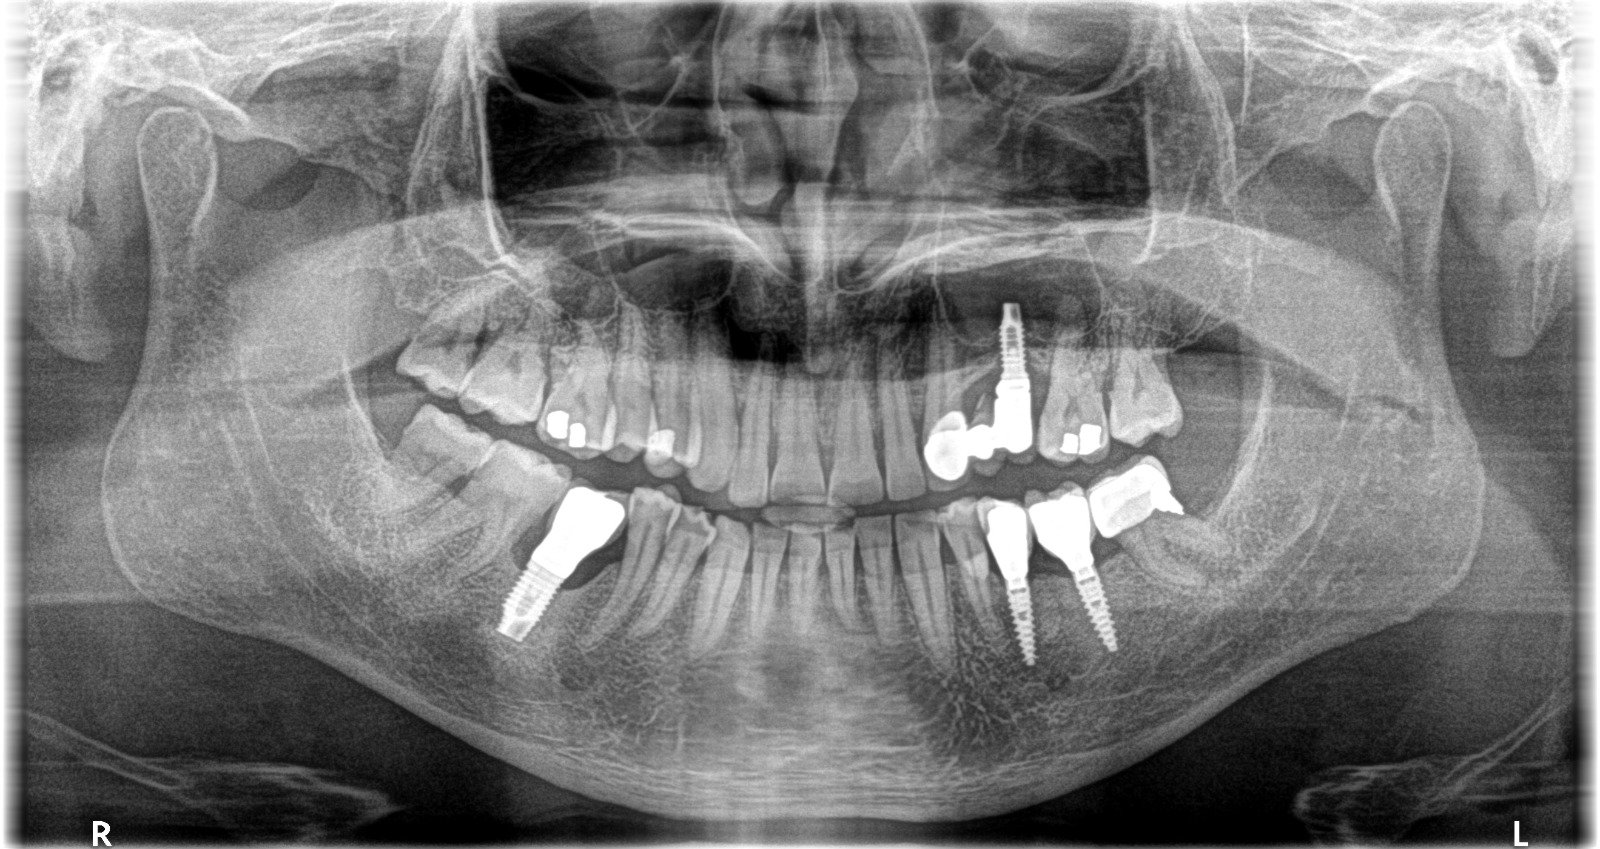

Queridos compañeros, me llega este caso de una persona muy especial y amiga de Barcelona. No manejo más información pero la panorámica es excelente. Gracias